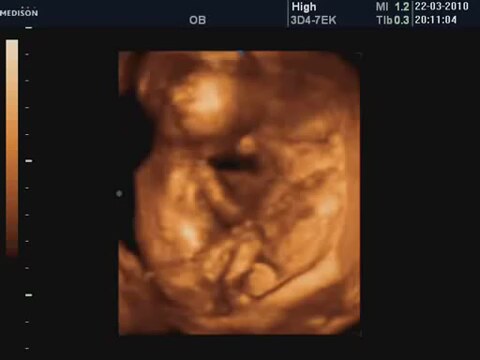

16 Haftalik Bebeğin 4 Boyutlu Ultrason Görüntüsü